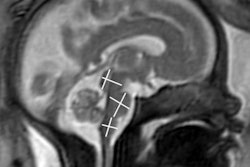

In addition to summarizing the key imaging findings of the disease in children, the update recommends four recent publications in the peer-reviewed literature.